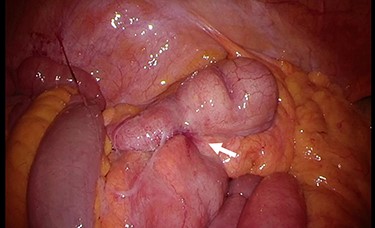

Therefore, surgery was performed. Intra-operatively, inflammation was observed in the terminal ileum (Fig. 4). We performed laparoscopic-assisted ileocecal resection with D3 lymphadenectomy. The resected specimen exhibited a yellowish change near the root of the appendix (Fig. 5). Microscopically, a nodular lesion with unclear boundaries was detected from the appendix root to the ileocecum, formed by fibrous cells, foamy histiocytes, foreign body giant cells and inflammatory cell infiltration (Fig. 6). There were no Michaelis–Gutmann bodies or malignancies. Based on these findings, the diagnosis was XA. No post-operative therapy was administered, and the patient remained uneventful for 20 months following surgery. The CA19–9 level decreased to 22.7 U/ml a month later and was within normal limits 20 months post-operatively.

Intra-operative findings. Inflammation is observed at the terminal ileum (arrow).